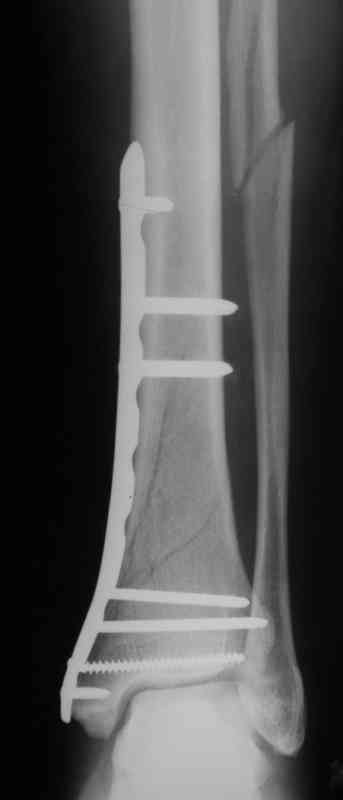

В приложении пример лечения аналогичного повреждения (плюс задний край).

Выполнил MIPO предизогнутой метафизарной LCP

Красиво получилось, поздравляю. Насчет немедленной полной нагрузки, как на гвозде, про что Алексей Семенистый говорит - будете разрешать сразу?

И все же немного критики:1) Вы добивались анатомичной репозиции, которая требует абсолютной стабильности, которая в свою очередь возможноа только в условиях межфрагментарной компрессии. Пластина уложена как мостовидная, не хватает стягивающнго винта. 2) есть укорочение малоберцовой кости, необхордимо восстановить ее длину! В таком виде я бы не стал разрешать раннюю нагрузку. Добавить самую малость: стягивающий винт и остеосинтез малоберцовой кости и больной может наступать сразу.